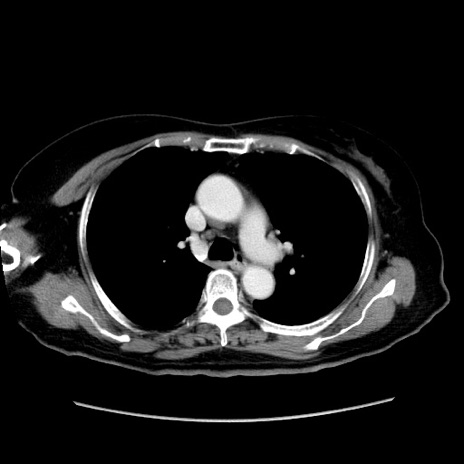

症例19(横断像)

【症例】80歳代女性

【主訴】下腹部痛

【現病歴】約8時間前より下腹部痛の出現あり、救急外来受診。

【既往歴】両側付属器切除

【身体所見】意識清明、下腹部正中に手術痕あり、その部位に一致して圧痛と反跳痛あり。腸蠕動音は亢進。

【データ】WBC 9300、CRP 0.15